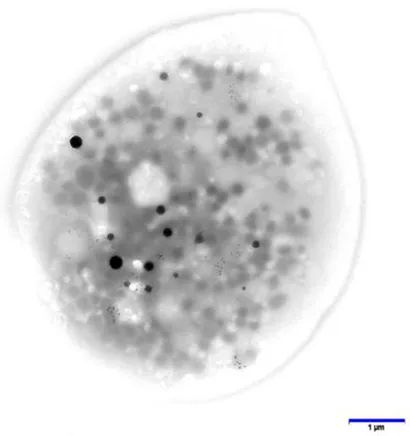

“Postural orthostatic tachycardia syndrome in post-COVID-19 long-hauler patients is associated with platelet storage pool deficiency”

Title: Postural orthostatic tachycardia syndrome in post-COVID-19 long-hauler patients is associated with platelet storage pool deficiency

Both POTS groups have δ-SPD, AKA dense (delta) granule storage pool deficiency. There also is a genetic version, but this was not assessed in this study.

Dense granules effect platelet activation and Alpha granules contain good stuff. I also add, mitochondria can travel between cells and I posit also help healing in the injured tissue.

But the problem I have is this: Both scenarios above point to platelets that are not “normal”: in long COVID POTS they may be chronically activated/exhausted, and in regular POTS they have intrinsic granule deficits. These features overlap with the concept of platelet senescence or aging. As platelets age (or undergo repeated activation), they lose granule content and responsiveness while gaining pro-inflammatory behavior.